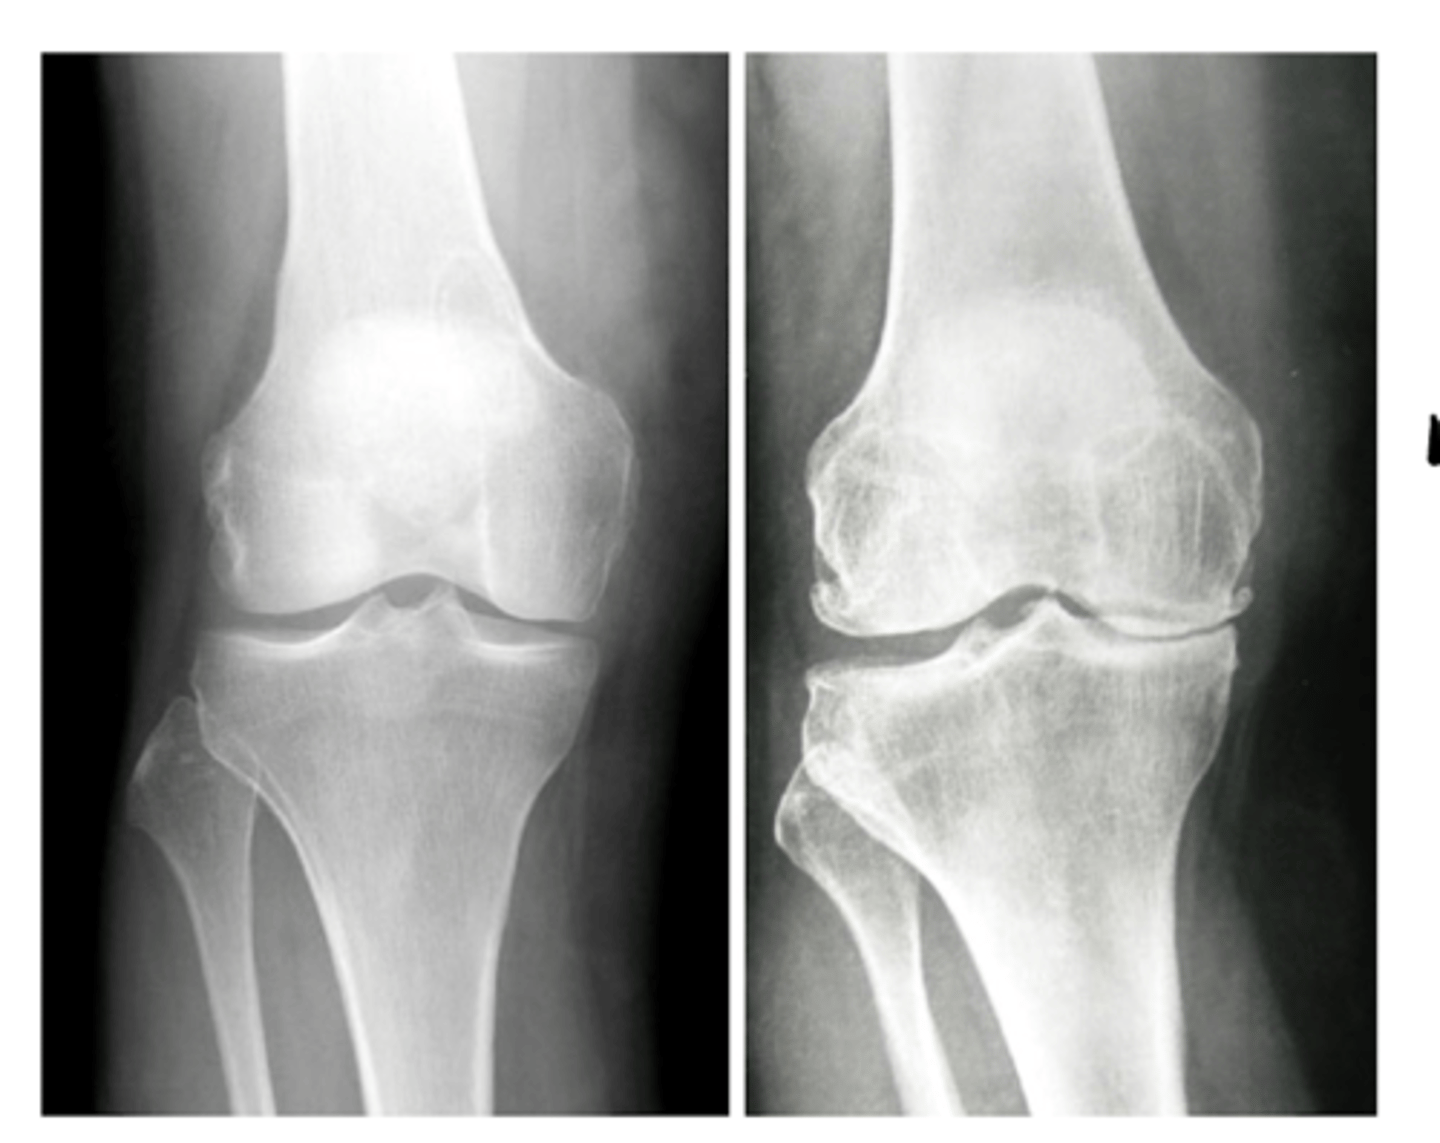

Hardening of the bone tissue at the joint line (often a primary indicator of OA)

1. "space" can be an indirect assessment of radiolucent cartilage

If we identify a loss of joint space on a plain film radiograph, what may this imply?

Loss of cartilage (primary indication of OA, along with bone spurs and sclerosis)

1. Muscles - atrophy - swelling (ex: swelling around the knee joint as seen in this image)